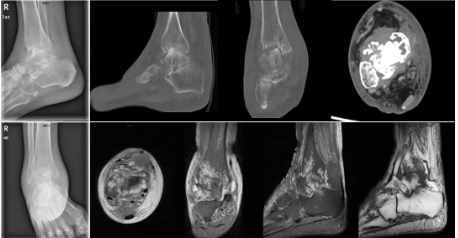

术前患者踝关节影像

钟环主任医师团队综合分析,患者想既要解决疼痛问题又能较好地保留踝关节的活动度,实施右侧全踝关节置术是最佳的选择。根据既往我院开展的踝关节置换手术经验,高先生的骨骼条件并无严重畸形,整个手术过程可以通过3D打印术前规划和辅助截骨获得更加精准的植入效果。最终,关节外科团队与患者及家属充分沟通,决定应用3D打印技术为高先生实施标准化假体的右侧全踝关节置换术。随后,钟环主任与手术团队成员在计算机3D模型前进行反复模拟演练,充分考虑标准化踝关节置换手术技术实施过程中的关键节点和术中潜在风险,准备了多套预案以应对术中情况的变化。